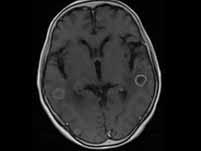

问题 男性,42岁,右肺门肿块伴血痰,细胞学证实小细胞肺癌,脑CT发现两个1.5cm左右孤立病灶,一般情况良好。若经治疗后达临床CR,下一步应该()

选项 A.吃中药防止复发 B.因已CR,无须治疗 C.生物免疫治疗 D.每3个月查一次并进行巩固化疗 E.加强锻炼,防止复发

答案 D